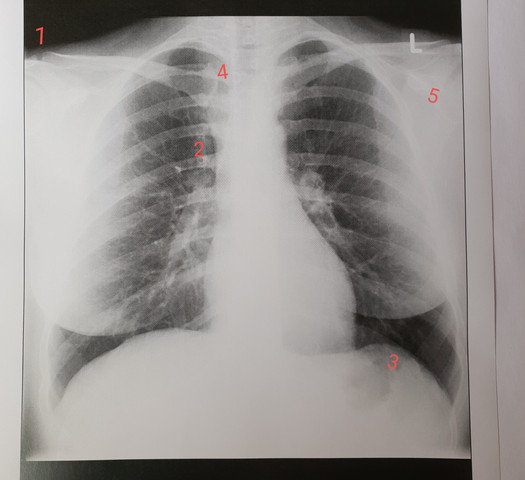

Röntgen Thorax Gefährlich : Herzinsuffizienz in Bildern

Herzinsuffizienz in Bildern

Funktionsweise eines CT-Scanners. Blutiger Erguss ( Hämatoperikard) Herzwandruptur (z.Schlagwörter:RöntgenstrahlenWilhelm Conrad RöntgenBereich:Kosten Beim Verdacht einer Herzinsuffizienz unterstützt eine Röntgen-Thorax-Untersuchung bei der Diagnose.Akute Milchglastrübungen entstehen beispielsweise bei Infektionen, alveolärer Hämorrhagie und Lungenödem.Pneumothorax: Symptome.Als Röntgen-Thorax bezeichnet man eine radiologische Untersuchung des Brustkorbs und der darin befindlichen Organe wie Lunge und Herz.Schlagwörter:Das RöntgenRöntgenbildNetDoktor.Eine Röntgenuntersuchung des Brustkorbs ist notwendig, um Schwere und Ausmaß der Erkrankung zu bestimmen.Pleurakuppenschwielen müssen von folgenden Differenzialdiagnosen abgegrenzt werden: Bei einer Dicke ab 3 mm im Röntgen-Thorax sollte eine Computertomographie zur weitergehenden Abklärung erfolgen. Der Röntgen-Thorax, also ein . Denn: Die Strahlen haben durchaus Nebenwirkungen.Schlagwörter:Das RöntgenRöntgenstrahlenDie Strahlen

Thorax-Magen bzw.Als Lungeninfiltrat bezeichnet man eine röntgenologisch sichtbare Verschattung (Röntgen-Thorax) bzw. Zuerst lässt sich die Lungenstauung röntgenologisch durch eine beginnende Flüssigkeitseinlagerung in .